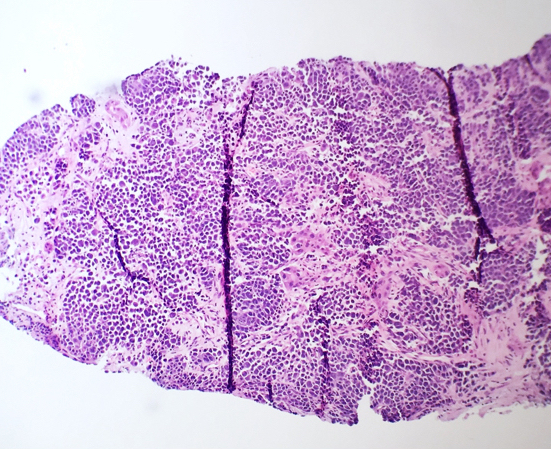

Frozen section description

- Osseous or extraosseous plasmacytomas, particularly if the patient is not known to have a history of plasma cell myeloma, may be sent for frozen section evaluation (Borczuk: Frozen Section Pathology, 1st Edition, 2021)

- Sites can include: mucosa of the upper respiratory tract, lymph nodes, thyroid, testes, breast, salivary gland and CNS (Int J Otolaryngol 2010;2010:302656)

- Morphology may range from monotonous plasma cells to more irregular, multinucleated or pleomorphic forms in more advanced myeloma

Frozen section images

Microscopic (histologic) description

- Core biopsy (Am J Clin Path 1987;87:342):

- Interstitial clusters, nodules or sheets of plasma cells